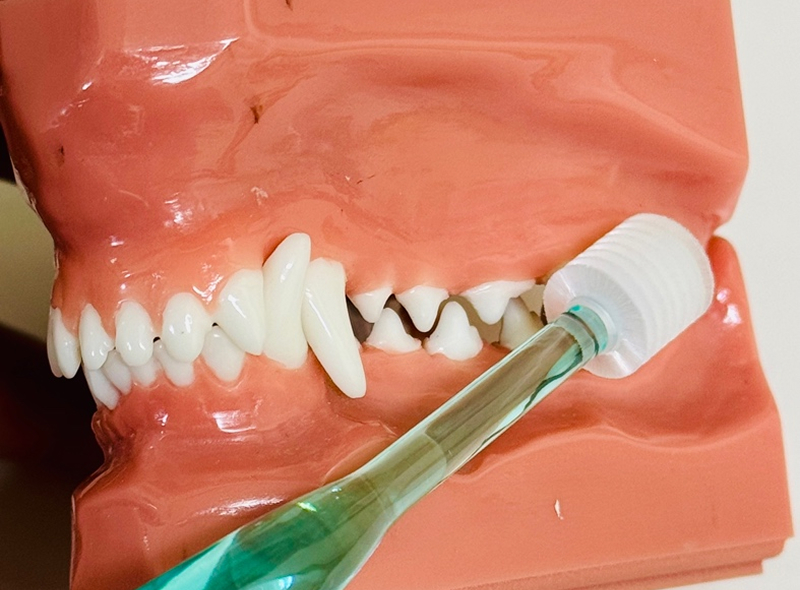

ご自宅での口腔ケア(ホームケア)

歯周病予防のためのホームケアや歯科治療後のホームケアは重要です。

プラークは2~3日で石灰沈着を起こし、歯石になっていきます。歯石が付着することでプラークがより一層付着しやすくなり、歯周病を進行させてしまいます。(歯石自体が歯周病の原因というわけではありません)

歯周病予防のためには病院での歯周病治療のみでなく、定期的なホームケアが重要です。

子犬、子猫のときから歯磨きの習慣を身につけておくといいでしょう。まずは指で歯に触れさせることから始めていきましょう。その際に褒めたり、ご褒美をあげることで歯を触らせることに抵抗がなくなります。次に指に装着するタイプのデンタルケアグッズを使用してみましょう。慣れてきたら歯ブラシを使用してみましょう。

当院でも様々なデンタルケアグッズをご案内しております。お気軽にご相談ください。